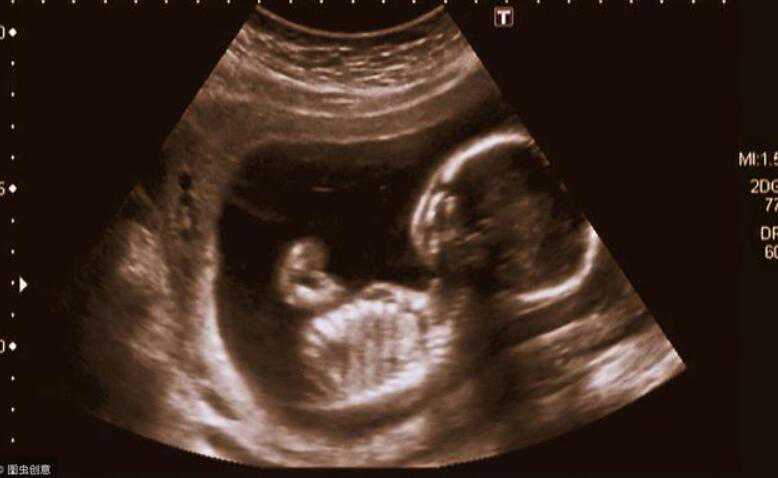

大家应该都知道,在正常情况下,一个胎儿的诞生是需要父亲的精子,以及母亲的卵子相结合而形成的,然后受精卵就会分裂成为胚胎,然后再进入到母亲的子宫里进行发育,

可是,试管婴儿确实由人工干预才能形成的,需要人工提取父亲的精子和母亲的卵子,在体外进行人工结合,然后在形成一个健康的胚胎,之后再由人工存入到母亲的体内,而这个时候,是很危险的,因为胚胎很容易在半路就夭折。

当胚胎发育好之后,就要进入母体了,这个过程会有些痛感,由冰冷的工具将胚胎移植子宫内,找到一个合适的位置进行着床,

等到了这一步,就意味着试管婴儿已经完成,也意味着你已经是一个妈妈了,要肩负起妈妈的使命和责任,保护好宝宝,